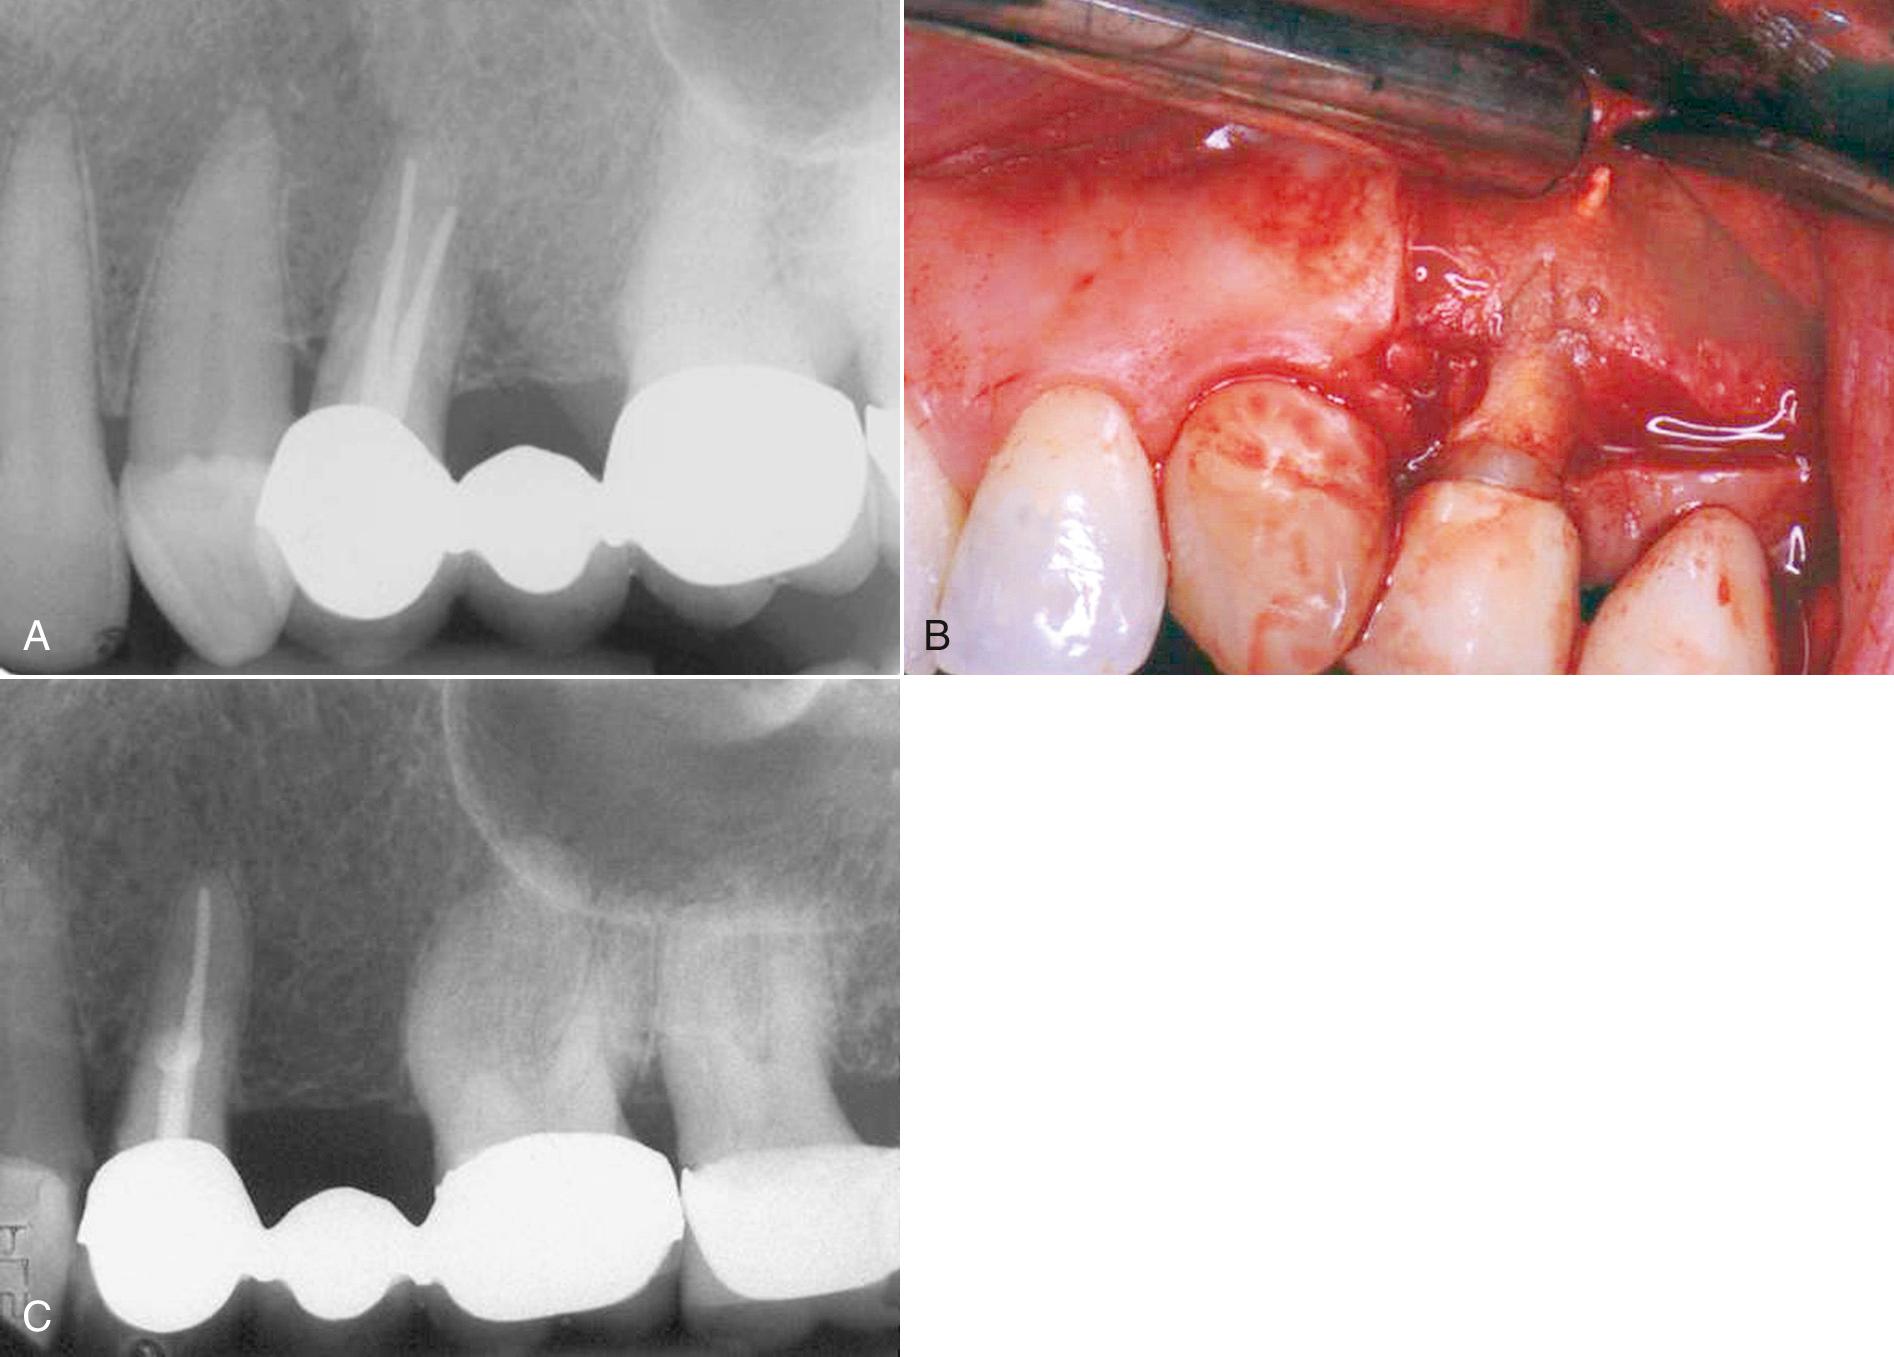

The success of apical surgery varies considerably depending on the reason for and nature of the procedure. With failed root canal treatment, retreatment often is not possible, or a better result cannot be achieved by a coronal approach. If the cause of the failure cannot be identified, surgical exploration may be necessary ( Fig. 18.2 ). On occasion, an unusual entity in the periapical region requires surgical removal and biopsy for identification ( Fig. 18.3 ). Indications for periapical surgery are discussed in the following sections ( Box 18.3 ).

Fig. 18.2, Surgical exploration. (A) The patient had persistent pain over the midroot region following what appears to be successful endodontic treatment. (B) Surgical exploration reveals perforation of the buccal root during the endodontic treatment with displaced gutta-percha. (C) Postoperative periapical film of surgical removal of the extruded gutta-percha and mineral trioxide aggregate seal.

Fig. 18.3, Surgical removal of pathosis. (A) The patient was referred for surgery because of an increasing radiolucent area after conventional endodontic treatment. Note the atypical nature of the radiolucent lesion, which indicates tissue submission should be done in conjunction with the apical surgery. (B) Treatment by apical surgery with amalgam retrograde seal, along with a biopsy of the associated tissue. The final diagnosis was cystic ameloblastoma.